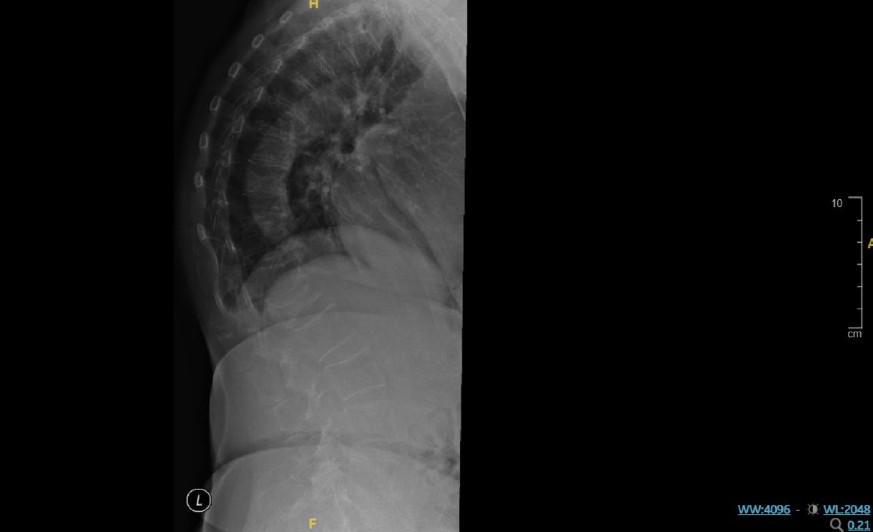

- Fell in January 2023 and sustained multiple fractures: vertebral, left proximal humerus, and right lateral malleolus.

- Imaging confirmed fractures involving L1, left proximal humerus, and right lateral malleolus. All were managed non-operatively.

X-ray